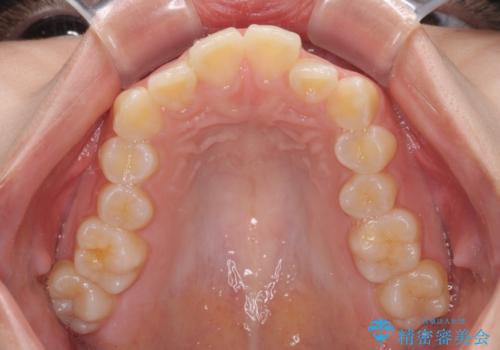

- 前歯の叢生を気にして来院された患者様です。

奥歯の咬み合わせを見ると、上顎が下顎に対して相対的に前方にあり、上下の前歯が接触していない状態でした。

咬み合わせを改善するためには、上顎臼歯を後方に移動させた咬み合わせにする必要があります。

インビザライン単体で改善することも可能ですが、咬合力が強く、単位で達成する可能性が低いと考えられたため、カリエール・ディスタライザーという補助装置を併用して、より確実性を上げることとしました。

奥歯の咬み合わせを改善しながら、並行してインビザラインで歯列を整えることとしました。